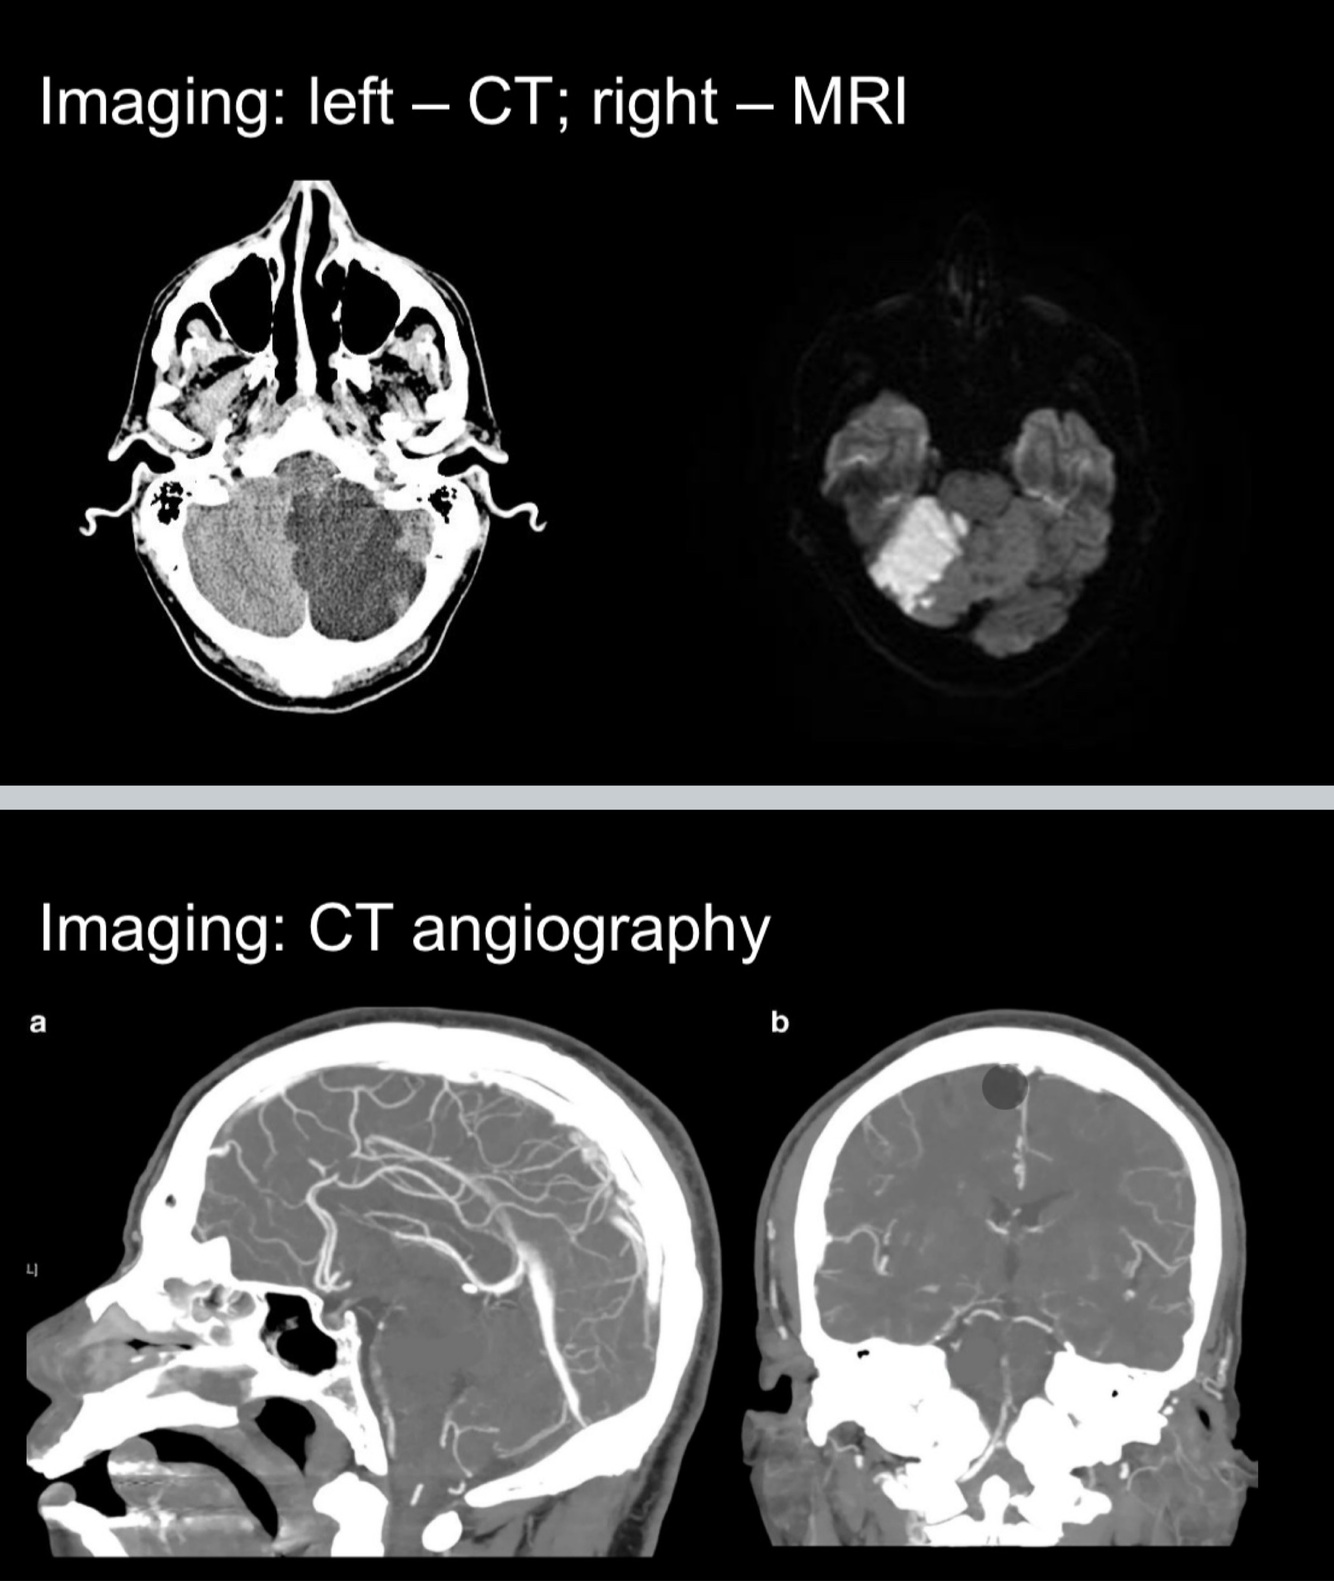

What does the CT + MRI demonstrate?

An old right posterior-inferior cerebellar artery (PICA) stroke and a subacute left PICA stroke

CT- The rest of the brain is NOT visible, suggesting that you are in the INFERIOR cerebellum (ie territory of AICA and PICA).

MRI- the temporal lobes ARE visible, suggesting that you are in the SUPERIOR cerebellum (ie territory of SCA).

CT- Region of hypodensity= infarct

MRI- Region of hyperdensity = infarct. In diffusion-

weighted MRI, infarcts lead to a lack of diffusion of

water molecules as Na/K pump breaks down,

leading to more intracellular water = bright signal.